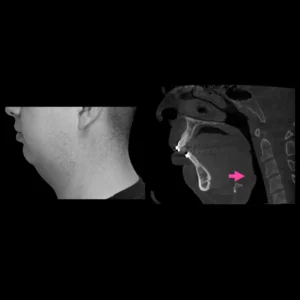

Apnea del sueño (por obstrucción maxilofacial)

Una de cada 10 personas adultas en México podría padecer apnea obstructiva del sueño, siendo este un factor de riesgo de hipertensión y enfermedades vasculares, los hombres presentan dos veces más probabilidad de padecer este problema.

Los neumólogos subrayan la necesidad de crear conciencia sobre la importancia de atender la apnea obstructiva del sueño, ya que, al ser común, las personas minimizan el problema por la creencia de que roncar es normal.

Los síntomas de la apnea son relativamente fáciles de identificar consisten en un ronquido continuo y ruidoso y pausas en la respiración al dormir.

La investigación del Síndrome de Apnea Obstructiva del Sueño, ha demostrado científicamente que la cirugía ortognática y/o de estructuras de los maxilares es una solución definitiva a este problema en pacientes que presentan deformidades dentofaciales.